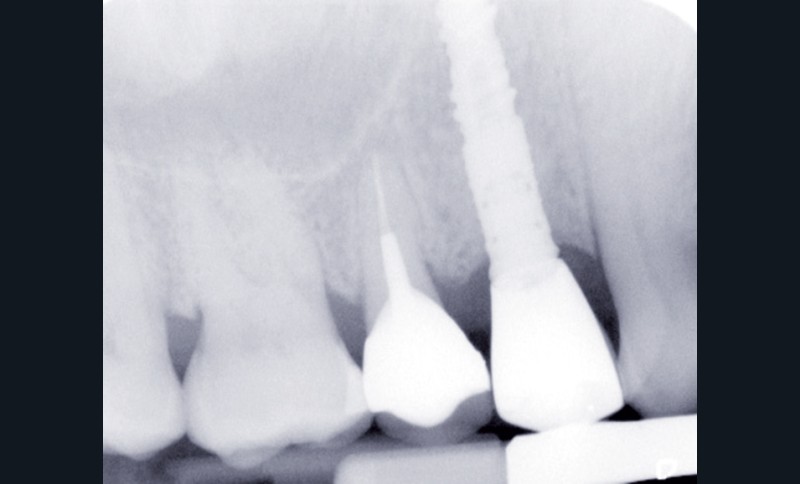

Le contrôle radiologique rétro-alvéolaire montre, quant à lui, une parfaite préservation de l’ostéointégration à 6 ans(fig. 3a et b).

Cette ostéointégration est confirmée par le Cone Beam(fig. 4a et b).